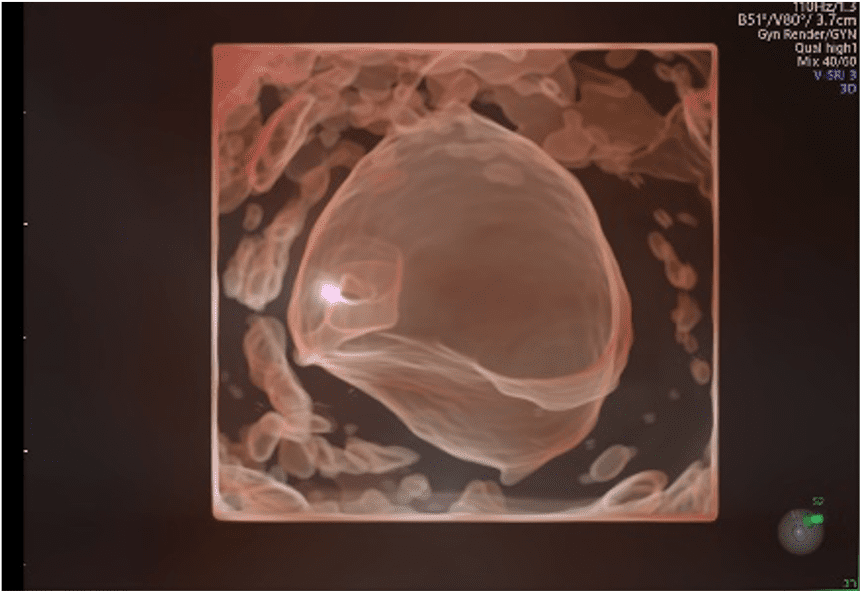

SonoAVC Follicle, Antral e General (Sonography Based Automated Volume Count Analysis): strumento avanzato, basato sulla tecnologia Volume Ultrasound con AI inside, che permette il riconoscimento automatico, semiautomatico ed interattivo dei follicoli

Software ADNEX a bordo macchina per la valutazione del rischio di cancro ovarico secondo le più recenti linee guida internazionali IOTA (International Ovarian Tumor Analysis) per poter fornire un counseling completo alle pazienti con patologia ovarica.

Uterine Trace: software per la ricostruzione automatica della cavità uterina.